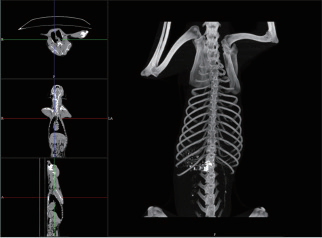

宠物转用影像处理技术

VR皮肤显示界面

• 皮肤通透

VR骨骼显示界面

• 骨骼轮廓清晰

MIP显示界面

• 剥离完整